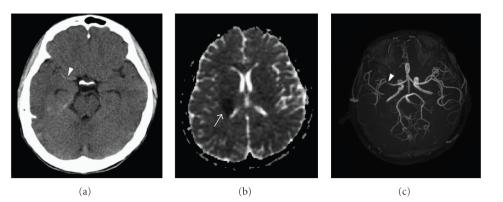

Stroke is a sudden onset neurological deficit due to a cerebrovascular event. In children, the recognition of stroke is often delayed due to the low incidence of stroke and the lack of specific assessment measures to this entity. The causes of pediatric stroke are significantly different from that of adult stroke. The lack of safety and efficiency data in the treatment is the challenge while facing children with stroke. Nearly half of survivors of pediatric stroke may have neurologic deficits affecting functional status and quality of life. They may cause a substantial burden on health care resources. Hence, an accurate history, including onset and duration of symptoms, risk factors, and a complete investigation, including hematologic, neuroimaging, and metabolic studies is the key to make a corrective diagnosis. A prompt and optimal treatment without delay may minimize the damage to the brain.

中风是一种由脑血管事件导致的突发性神经功能缺损。在儿童中,由于中风发病率低且缺乏针对该病症的特异性评估措施,中风的识别往往会延迟。小儿中风的病因与成人中风有显著差异。在治疗方面缺乏安全性和有效性数据是治疗中风患儿时面临的挑战。小儿中风幸存者中近一半可能存在影响功能状态和生活质量的神经功能缺损。它们可能给医疗资源带来巨大负担。因此,准确的病史,包括症状的发作和持续时间、危险因素,以及全面的检查,包括血液学、神经影像学和代谢研究,是做出正确诊断的关键。及时且无延迟地进行迅速且最佳的治疗可将对大脑的损伤降至最低。